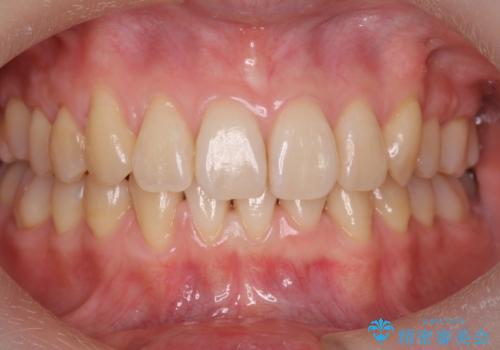

前歯のがたつき、八重歯 インビザラインで抜歯矯正

- 前歯のがたつきを主訴に来院。

下の前歯は生まれつき1本少ない状態でした。

左上の犬歯が入りきらずねじれており、かみ合わせもずれていました。

左上の小臼歯を1本抜いて治療しています。

前歯は内側に傾いており(ラビッティング)、過蓋咬合(深いかみ合わせ)を呈していました。

難しい治療でしたが綺麗に咬み合わせることができ、また前歯もしっかり当たるように治療できました。